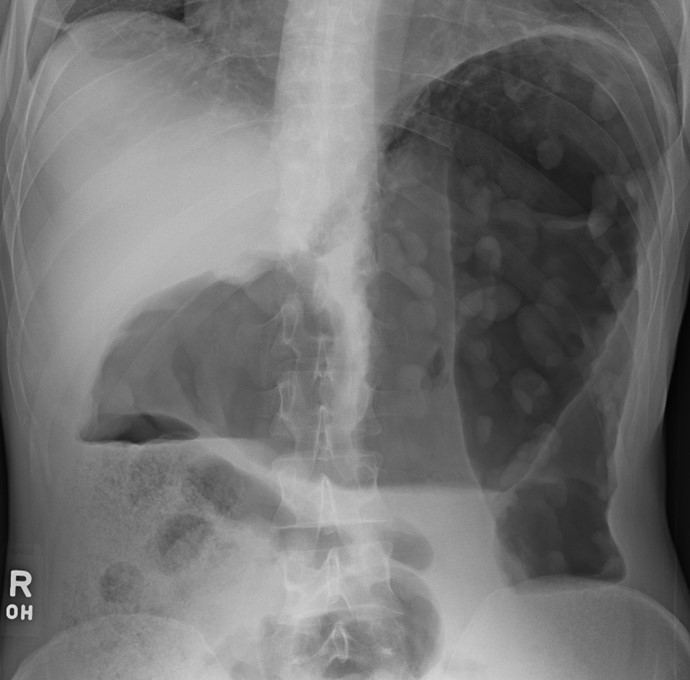

A 44-year-old previously healthy woman comes to the office due to 2 months of low-grade fever, abdominal pain, and intermittent bloody diarrhea.  Her pain has dramatically increased over the past 48 hours.  The patient takes no medications and has no allergies.  She has lost 4.5 kg (10 lb) over the past 8 weeks.  She has no recent travel history.  Temperature is 38.9 C (102 F) , blood pressure is 102/70 mm Hg, pulse is 118/min, and respirations are 22/min.  Examination shows pale and dry mucous membranes.  Abdominal examination reveals distension and diffuse tenderness.  Laboratory results are as follows: A 44-year-old previously healthy woman comes to the office due to 2 months of low-grade fever, abdominal pain, and intermittent bloody diarrhea.  Her pain has dramatically increased over the past 48 hours.  The patient takes no medications and has no allergies.  She has lost 4.5 kg (10 lb)  over the past 8 weeks.  She has no recent travel history.  Temperature is 38.9 C (102 F) , blood pressure is 102/70 mm Hg, pulse is 118/min, and respirations are 22/min.  Examination shows pale and dry mucous membranes.  Abdominal examination reveals distension and diffuse tenderness.  Laboratory results are as follows:   HIV test is negative.  X-ray of the abdomen is shown below:   Which of the following interventions is indicated at this time? A) Colonoscopy B) Intravenous ganciclovir C) Intravenous methylprednisolone D) Pain control with intravenous opioids HIV test is negative.  X-ray of the abdomen is shown below: